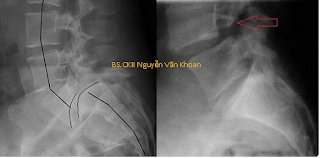

Trượt đốt sống do khuyết eo đốt sống mức độ nặng và trượt đốt sống do loạn sản đốt sống là một dạng khác với trượt đốt sống mức độ nhẹ do khuyết eo đốt sống. Gọi là trượt nặng khi di lệch hơn 50% bề mặt thân đốt sống. Trượt nặng thường kèm theo gù vùng thắt lưng-cùng. Trượt nặng hiếm gặp hơn trượt nhẹ, trong các trường hợp trượt đốt sống do khuyết eo đốt sống thì trượt nặng chỉ chiếm dưới 10% và thường gặp ở lứa tuổi thanh thiếu niên.

Có 5 mức độ trượt theo tác giả Meyerding, dựa vào phim x quang:

Độ 1: trượt 0-25% thân đốt sống.

Độ 2: trượt 26-50% thân đốt sống.

Độ 3: trượt 51-75% thân đốt sống.

Độ 4: trượt 76-100% thân đốt sống.

Độ 5: trượt hoàn toàn, đốt trên hoàn toàn rơi khỏi bề mặt thân đốt dưới.